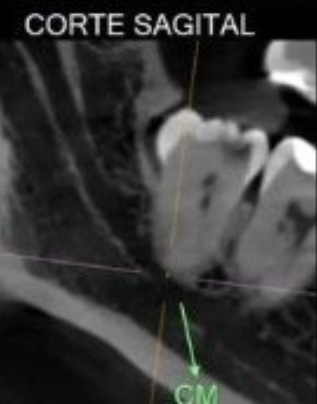

Veja alguns casos de sucesso